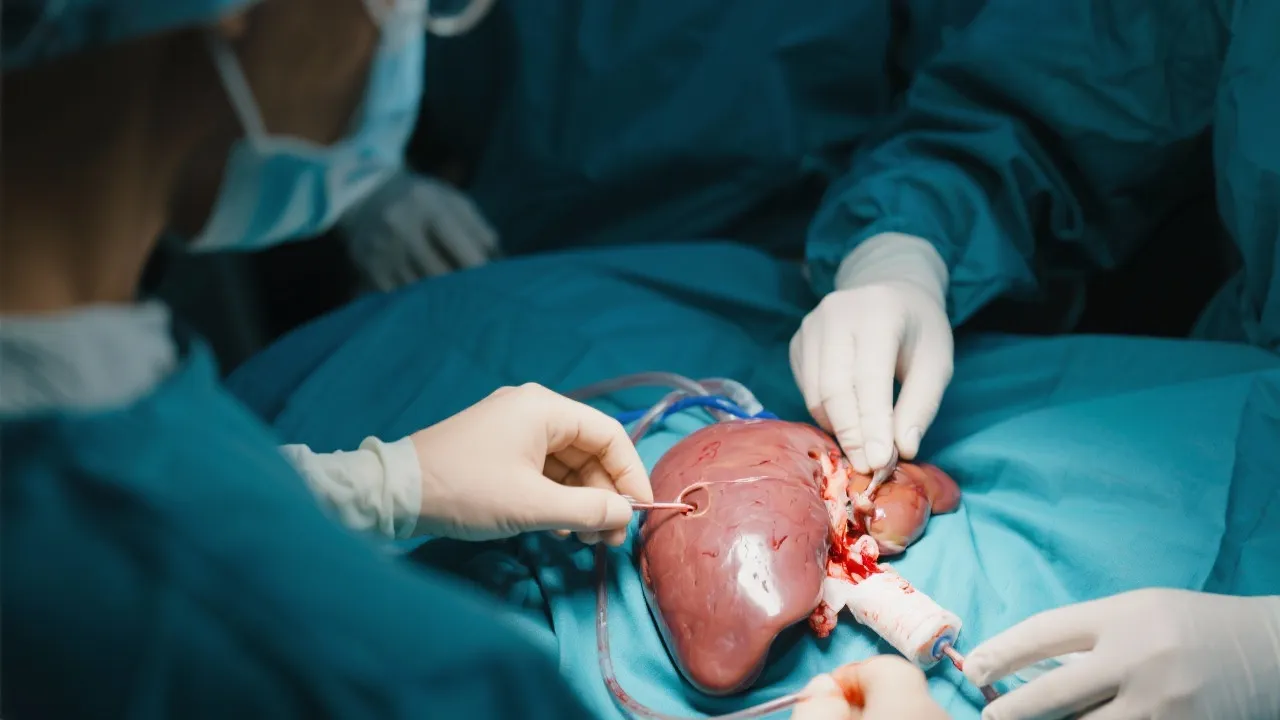

Understanding Hepatitis E and Liver Transplant

Understanding Hepatitis E and Liver Transplants

Understanding Hepatitis E and Liver Transplants

Understanding Hepatitis E and Liver Transplants

Understanding Hepatitis E and Liver Transplants

Hepatitis E and Liver Transplant

Understanding Hepatitis E and Liver Transplant

Understanding Hepatitis E and Liver Transplants

Navigating Hepatitis E and Liver Transplant

Navigating Hepatitis E Liver Transplants

Hepatitis E and Liver Transplant Insights

Hepatitis E and Liver Transplant